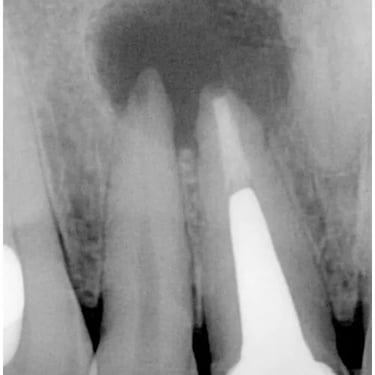

Quiste Periapical

Un quiste periapical es una cavidad llena de líquido en la punta de la raíz del diente, generalmente resultado de una infección crónica.

Los pacientes pueden notar una hinchazón sin dolor en la encía.

El tratamiento incluye el tratamiento de conducto y, a veces, la extirpación quirúrgica del quiste. Si no se trata, el quiste puede crecer y causar complicaciones.